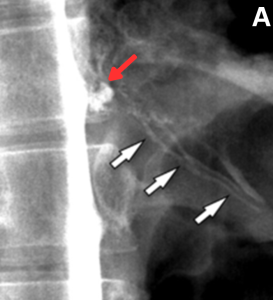

Fig 22: Figure A: Sagittal CT image of the thoracic spine shows a discogenic spur (red arrow).

Figure B: Sagittal T2-weighted image shows a discogenic spur with an associated anterior epidural collection (white arrows). Flow-related artefact is seen at the level of the spur – ‘Flow void’ sign (green arrow).

Figure C: Sagittal decubitus CT myelogram shows contrast from the subarachnoid space (yellow arrow), entering into the epidural space (black arrow).